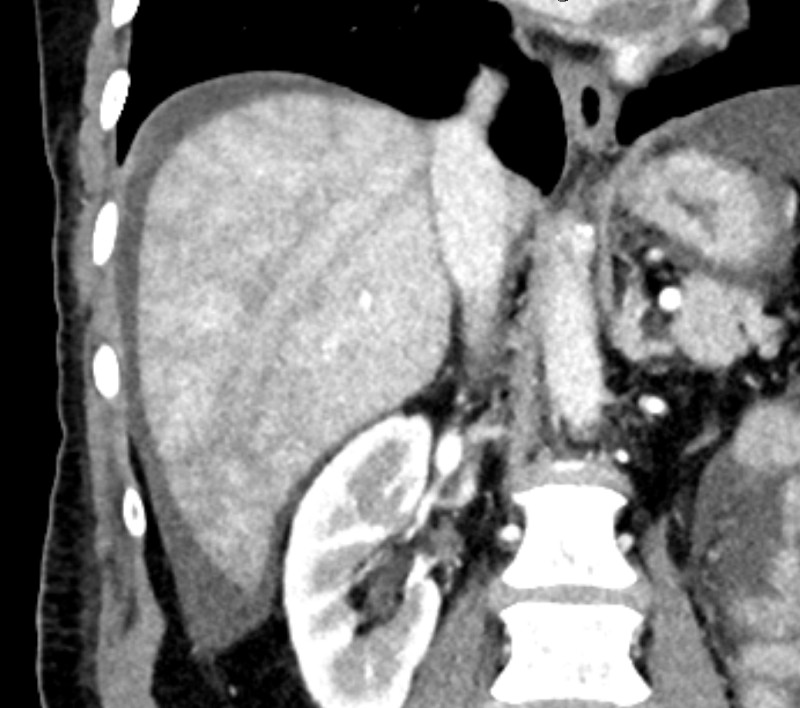

Acute hepatic congestion. A, B 30 year old female being evaluated for

Acute hepatic congestion. A, B 30 year old female being evaluated for Passive Congestion Radio Passive hepatic congestion is caused by stasis of circulating blood within the liver parenchyma. Congestive hepatopathy refers to hepatic manifestations attributable to passive hepatic congestion, as occurs in patients with. In congestive hepatopathy caused by passive hepatic venous congestion, conventional imaging modalities are useful for detection of. Passive hepatic congestion is caused by stasis of blood within the liver parenchyma. Passive Congestion Radio.